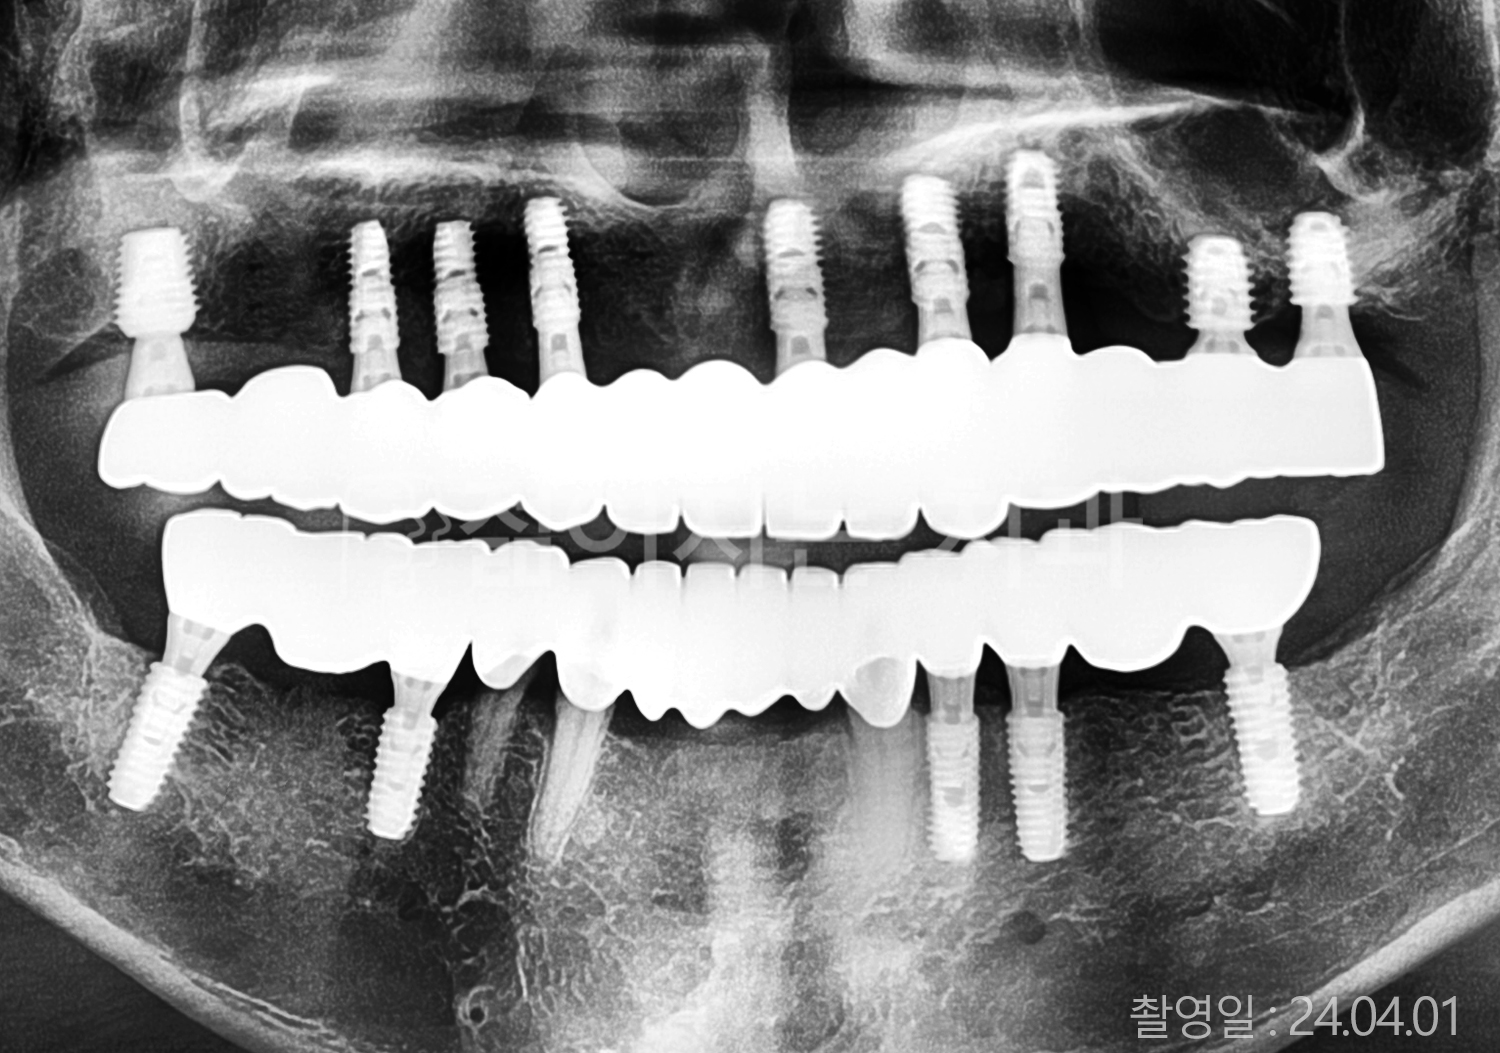

• 40대 전체치아 10개 이상 임플란트

• 70대 당뇨 전체치아 10개 이상 임플란트

• 60대 전체치아 10개 이상 임플란트

• 60대 고혈압, 당뇨, 고지혈증 전체치아 10개 이상 임플란트

• 50대 전체치아 10개 이상 임플란트

• 70대 고혈압, 당뇨 전체치아 10개 이상 임플란트

• 60대 고혈압 전체치아 10개 이상 임플란트

• 50대 고혈압, 당뇨, 고지혈증 전체치아 10개 이상 임플란트

• 60대 고혈압, 고지혈증 전체치아 10개 이상 임플란트